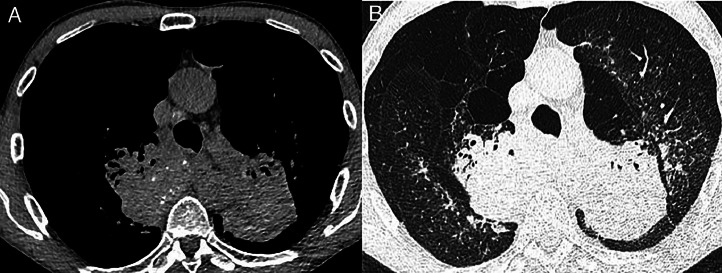

Abstract Image